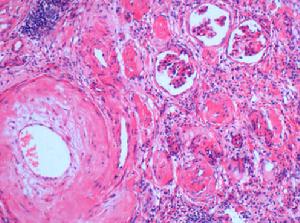

鼻咽喉模式圖大多數患者鼻出血可能是腫瘤組織中血管缺乏肌層,基質中缺乏彈性纖維,出血持續時間和發生率與血管的口徑大小、數目、組織的成熟情況無相關;鼻出血與腫瘤血管脆度相關。纖維成分增多,鼻出血傾向將降低。梁建鋼等認為腫瘤豐富的薄壁血竇,畸形較大的血管伴管壁平滑肌和彈性纖維發育不全以及繼發性血栓的形成也是鼻出血的重要因素。Wang等認為鼻出血與腫瘤中無去甲腎上腺素神經分布,不能引起血管收縮有關。腫瘤中央部組織越成熟,腫瘤的進化時間就越長,鼻塞持續時間也越長。Luiz等和Liang等對腫瘤中央部的組織分析認為腫瘤越大,其中的血管和細胞數目就越少,但組織的成熟度和血管的口徑較大,腫瘤中央部組織成熟度和腫瘤擴展能力有關係。Luiz等認為腫瘤中央部分纖維成分越多,血管和細胞數目就越少。